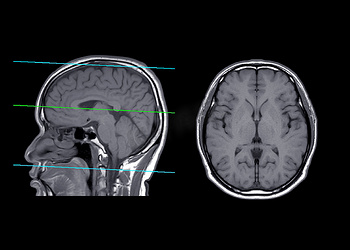

脳 MRI 3D : 正常解剖学e-Anatomy。

弁護士 小松亀一法律事務所_交通事故_MRI・CT写真の切り口用語解説。

ヘリカルCTは横断面だけではなく矢状面や冠状面も作ることができます!ふかつ泌尿器科・皮ふ科クリニック。